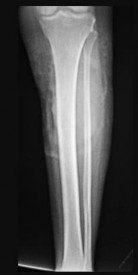

Figures 9a through 9d are the anteroposterior and lateral radiographs, CT scan, and technetium bone scan of a 12-year-old boy who has experienced 7 months of pain in his lower leg. The pain limits his ability to participate in sports and he is having difficulty sleeping. He is afebrile, and laboratory study findings including an erythrocyte sedimentation rate, C-reactive protein, and complete blood count are within normal limits.

The images and clinical history support a diagnosis of osteoid osteoma, which most commonly occurs in adolescence. Although these lesions can be seen in any bone, they are usually located in the femur and tibia. The significant inflammatory response to this tumor is secondary to high levels of prostaglandin production. Characteristic night pain is relieved with nonsteroidal anti-inflammatory drugs (NSAIDs) or by aspirin.

Radiographic images show thickened bone and a small central nidus. Thin-cut CT scan is the imaging of choice to visualize the nidus. A bone scan is associated with uptake but is not specific. Treatment options include expectant management with NSAIDs and observation under the premise that these lesions eventually burn out. Contemporary treatment involves RFA. Historically, these lesions were treated with en bloc resection; however, this technique has largely fallen out of favor because of the high efficacy and comparative low morbidity associated with RFA.

When an osteoid osteoma occurs in the spine, it is located in the posterior elements, and paraspinal pain and scoliosis often are present.